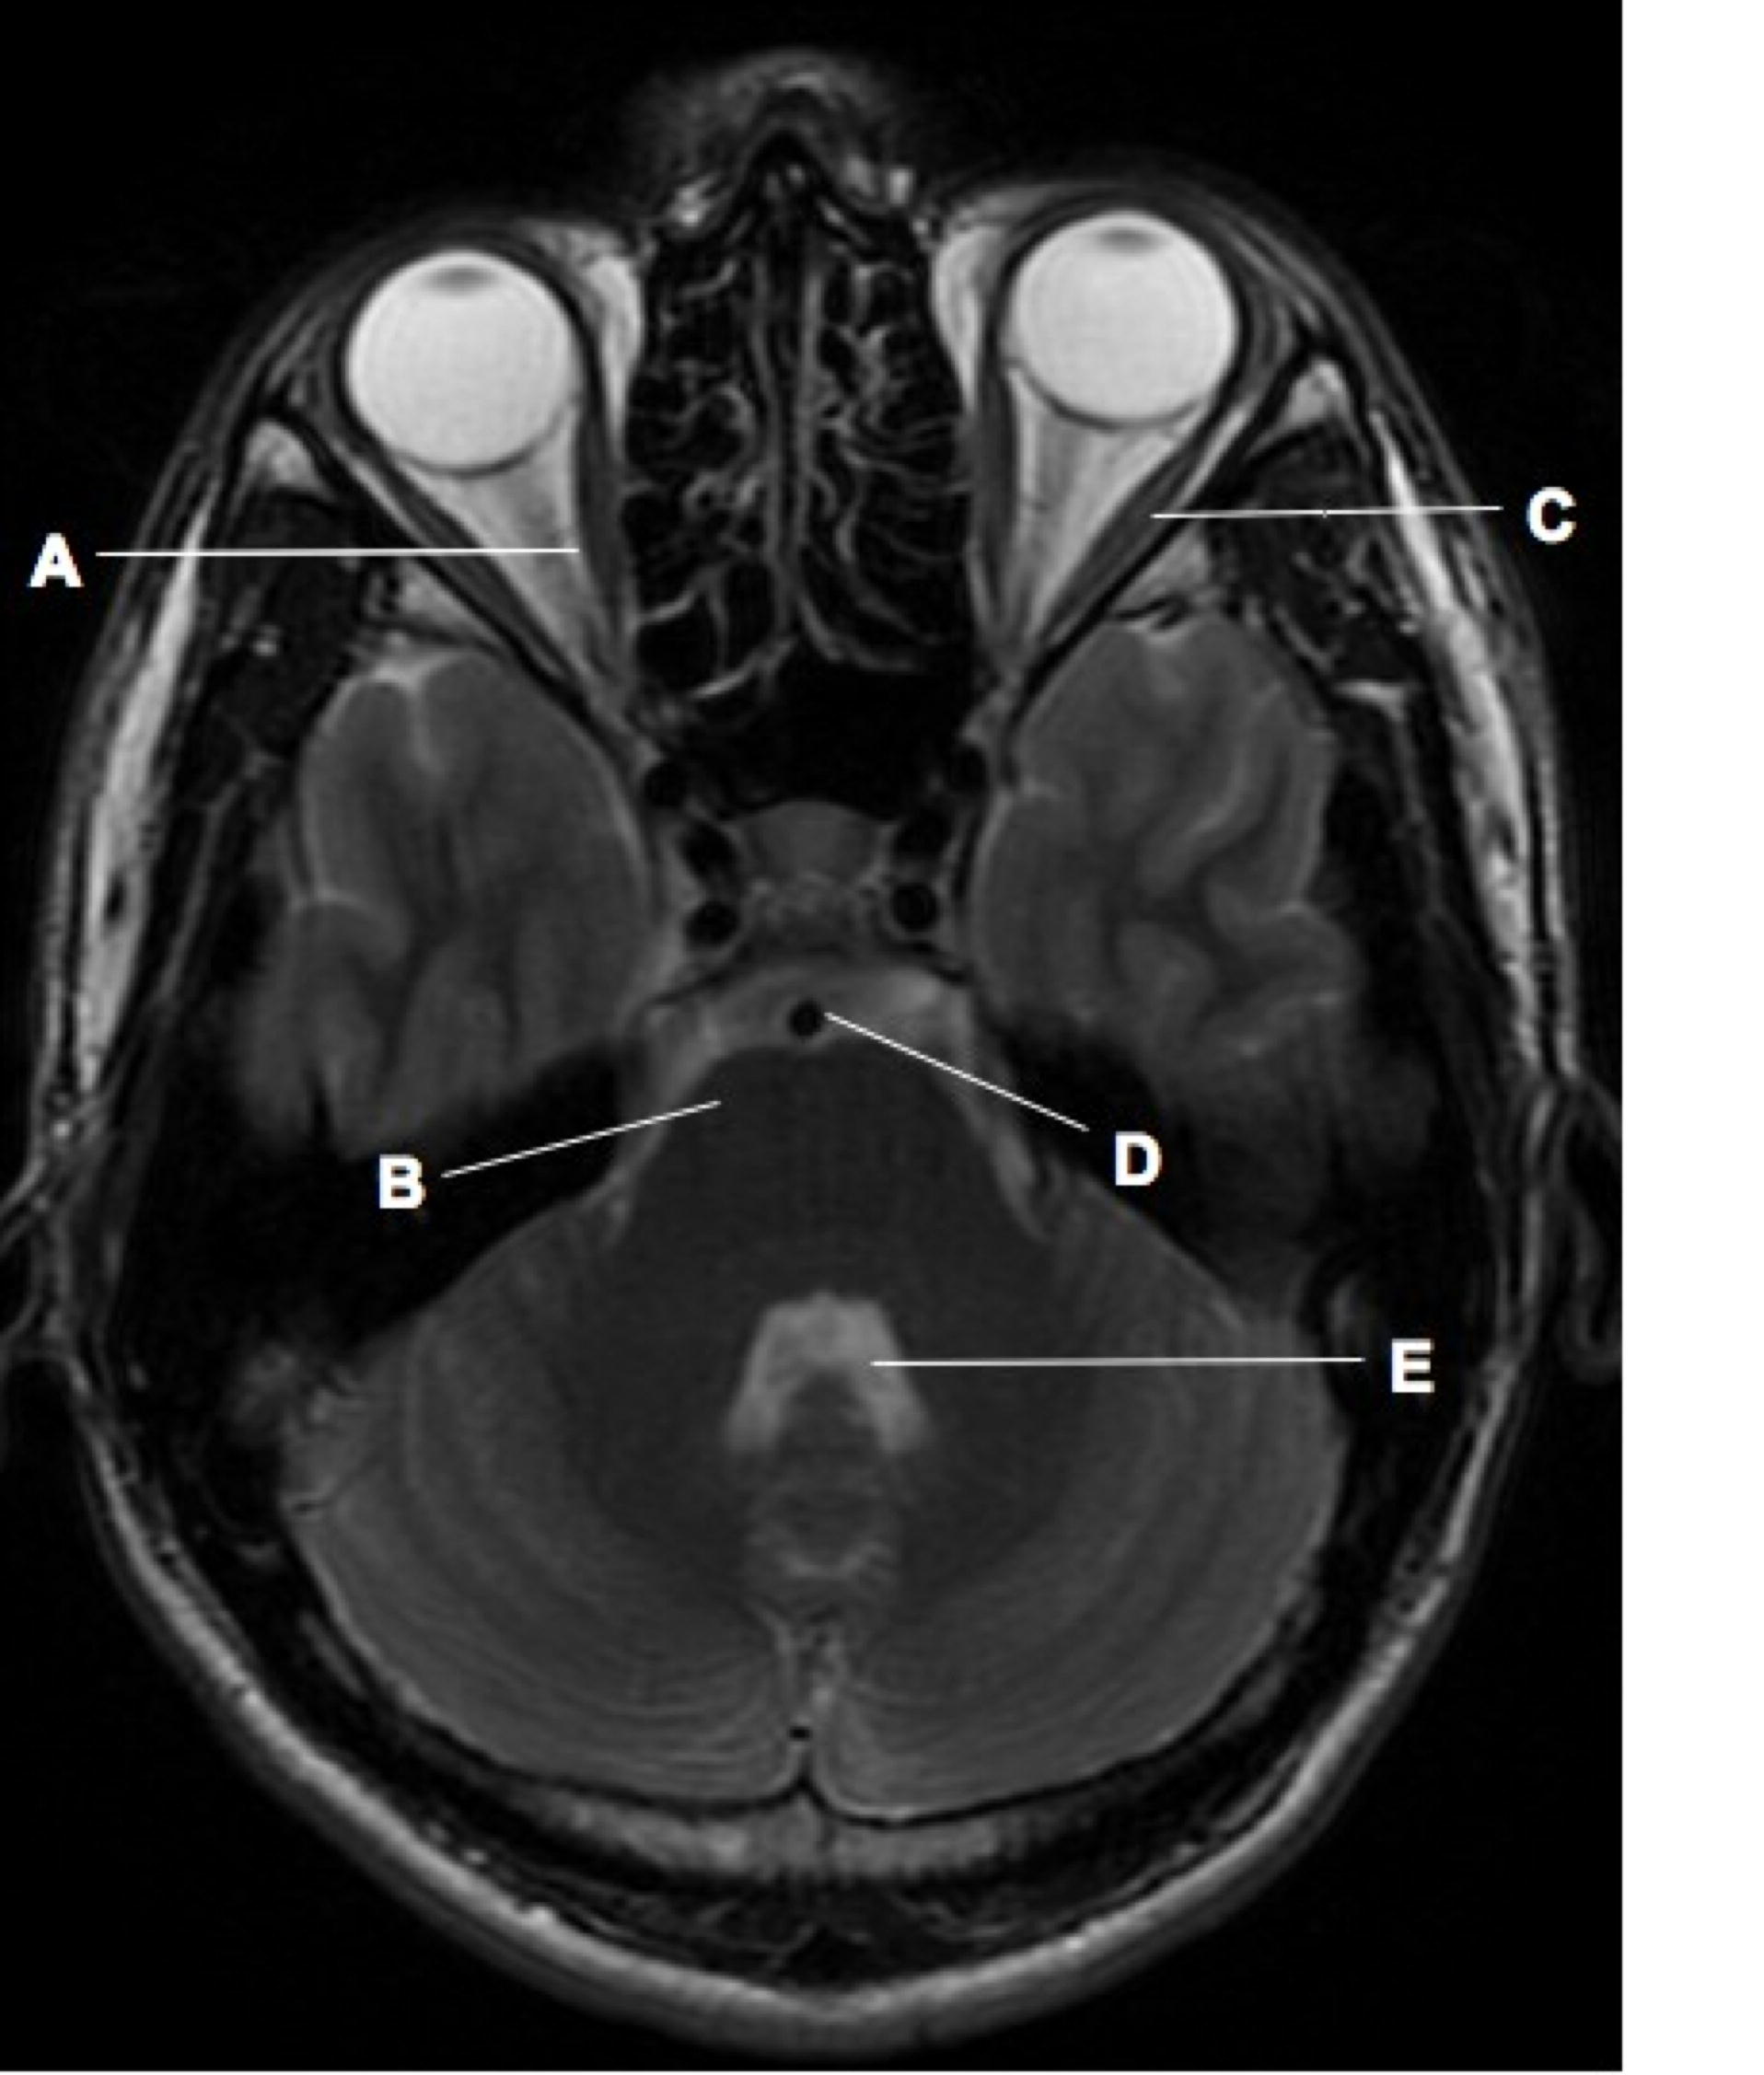

Discover the core differences between the axial skeleton and appendicular skeleton. Learn how these two systems—comprising the skull, spine, rib cage, and limbs—work together to support body structure, protect vital organs, and facilitate movement. Explore the functional anatomy of the human skeletal system and how these distinct frameworks ensure structural stability and mobility throughout your daily activities.